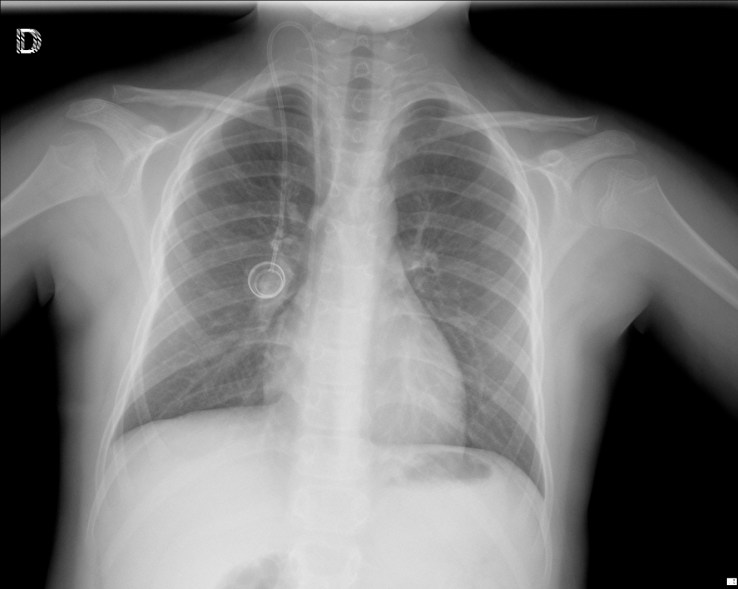

CASO: sospecha de neumonía.

Hallazgos:

- En un principio podríamos decir que existe un aumento de densidad retrocardiaco que podría ser compatible con condensación neumónica a dicho nivel, sin embargo estamos ante una placa poco inspirada, lo cual puede llevarnos a cometer errores diagnósticos.

- Se recomendó volver a realizar la radiografía, observar a continuación:

Ya no se observa el aumento de densidad retrocardiaco, la placa es normal.

INSPIRACIÓN: Una placa bien inspirada es aquella en la que se observar 6-7 arcos costales anteriores o 10-11 arcos costales posteriores. Lo contrario puede producir imágenes falsas de condensaciones o de seudocardiomegalia.